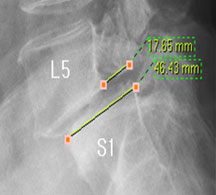

모커리한방병원 위 뼈가 50%정도 밀려나간 모습 이미지

척추전방전위증은 척추 주변, 특히 척추 후방에 있는 후관절 주변의 근육과 인대 그리고 후관절 자체가 퇴행되어 척추 뼈를 제대로 붙잡아 주지 못해 위아래 척추 뼈가 앞뒤로 밀려 나가면서 발생하는 척추질환을 말합니다.